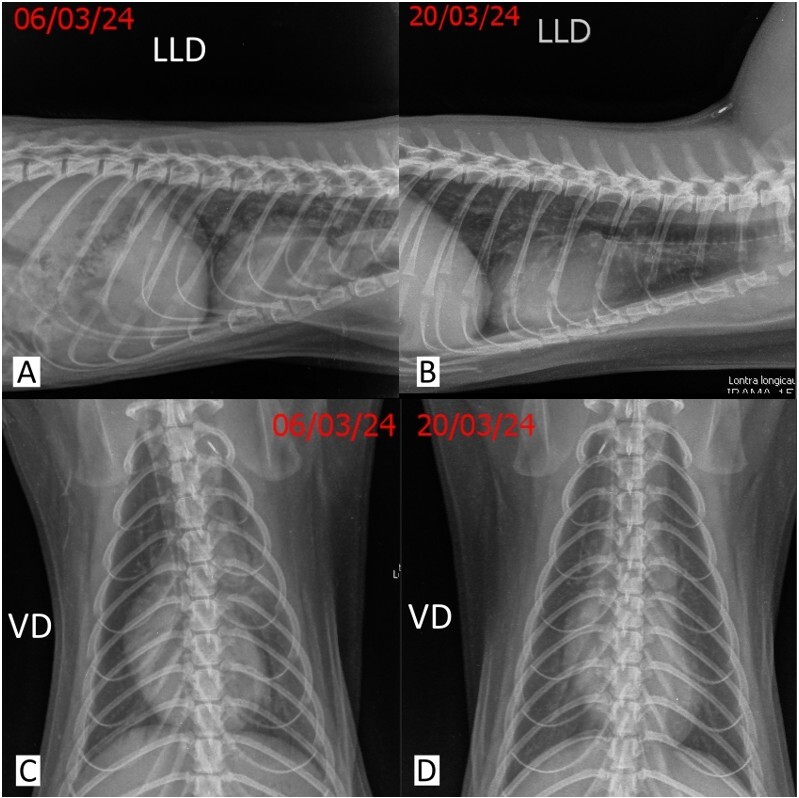

Clostridium perfringens alpha toxin (CPA) is an important enterotoxemic pathogen linked to gastrointestinal disorders and previously associated with pulmonary disease in other mammals. A young female neotropical otter presented with lethargy, anorexia and steatorrhea, which developed within 24 hours. Veterinary care was provided under anesthesia, during which dehydration, intestinal hypermotility and pulmonary crackling sounds were identified. Hematological tests revealed normochromic normocytic anemia, and a quantitative RT-PCR assay for Clostridium perfringens alpha toxin detected a markedly elevated CPA count (43,789 copies of pathogen DNA/uL) in fecal samples, confirming the diagnosis. An abdominal ultrasound exhibited intestinal gas and mucous fecal contents, with normal wall stratification and evolving peristalsis. Chest X-rays and bronchoscopy revealed diffuse serous secretion associated with an underlying inflammatory process, predominantly affecting the left lung. Treatment included hydroelectrolyte replacement, analgesia, antibiotics, and antiemetics, with close monitoring during the critical stage. The patient improved gradually, with regression of clinical signs and the emergence of innate behaviors, and was discharged to the original enclosure after two weeks, supported by updated test results. In conclusion, this study analyzes and details the veterinary approach, diagnosis, and treatment of an acute infectious enteric condition with pulmonary involvement in a neotropical otter under human care.